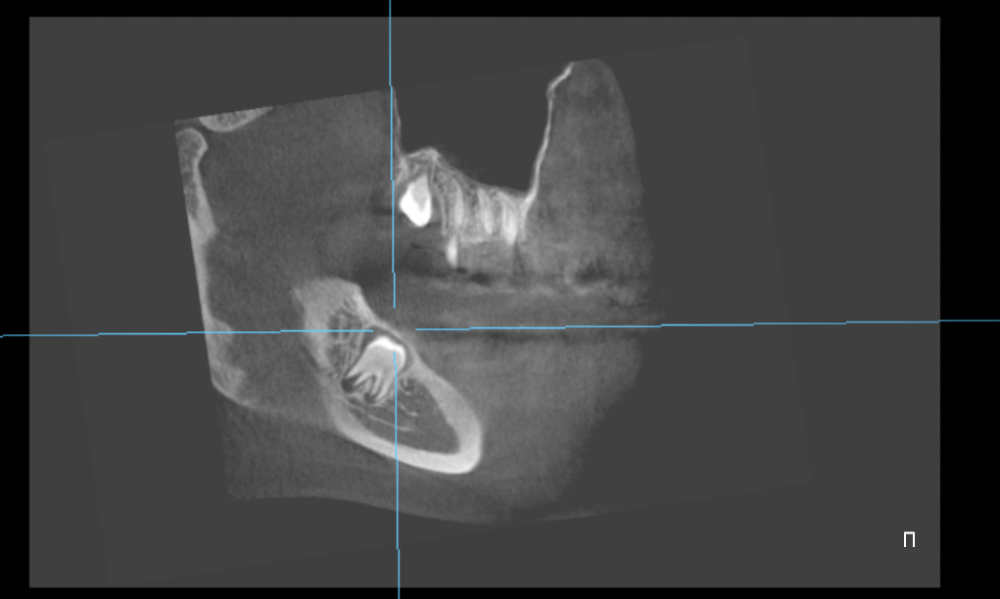

Irouil Опубликовано 1 мая, 2022 Поделиться Опубликовано 1 мая, 2022 59 минут назад, Faggott сказал: @Irouil, если результаты КТ действительно нужны для ответа на вопросы 2 и 3, то я загружу их 3 мая, когда выкуплю диск и найду дисковод. Если КТ необходимо для общей оценки ситуации (?), то, может быть, вы согласитесь дать более абстрактный совет? ? КТ позволяет оценить расположение зуба относительно возможного расположения язычного нерва. Сам нерв на КТ не виден, но существует примерная вероятность его расположения в определённых областях в проекции местоположения нижнего зуба мудрости. Таким образом, КТ позволяет оценить насколько высока вероятность повреждения нерва при удалении нижнего зуба мудрости. Наличие положительной динамики в Вашем случае - очень хороший знак, вероятнее всего повреждение тракционное, то есть нерв просто растянут, но не нарушена его целостность. 1 Ссылка на комментарий

Faggott Опубликовано 3 мая, 2022 Автор Поделиться Опубликовано 3 мая, 2022 01.05.2022 в 21:50, Irouil сказал: Покажите КТ @Irouil, ссылка на DICOM-файлы из КТ: https://drive.google.com/file/d/1zzESnhJBWdFfQzYsPNaK6rfdAGsnEAcu/view?usp=sharing А это скрины 8-к (хотя я не уверена, что это нужные скрины) //было бы так хорошо, если бы мне кто-то раньше сказал, что КТ бесплатно высылают на почту (и высылают образ диска с программами и файлами, а не "файлы, которые вы сами открыть не сможете") и что на факультете, где есть ЭВМ и древние компы с линуксом, нет компов с дисководами //зато теперь у меня есть диск, который мне, к сожалению, некуда вставлять Ссылка на комментарий